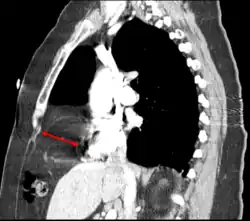

CT of the chest demonstrates a Morgagni hernia (red arrow)

This rare anterior defect of the diaphragm is variably referred to as a Morgagni, retrosternal, or parasternal hernia. Accounting for approximately 2% of all CDH cases, it is characterized by herniation through the foramina of Morgagni which are located immediately adjacent and posterior to the xiphoid process of the sternum.[4]